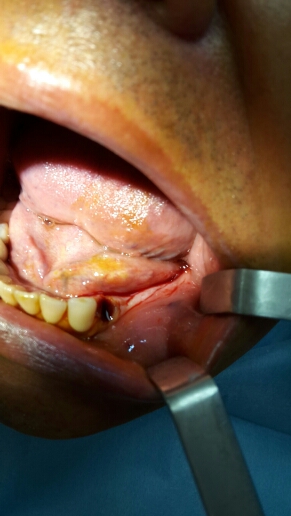

İmplant yapım aşaması

Implant yapım aşaması 3

Implant yapım